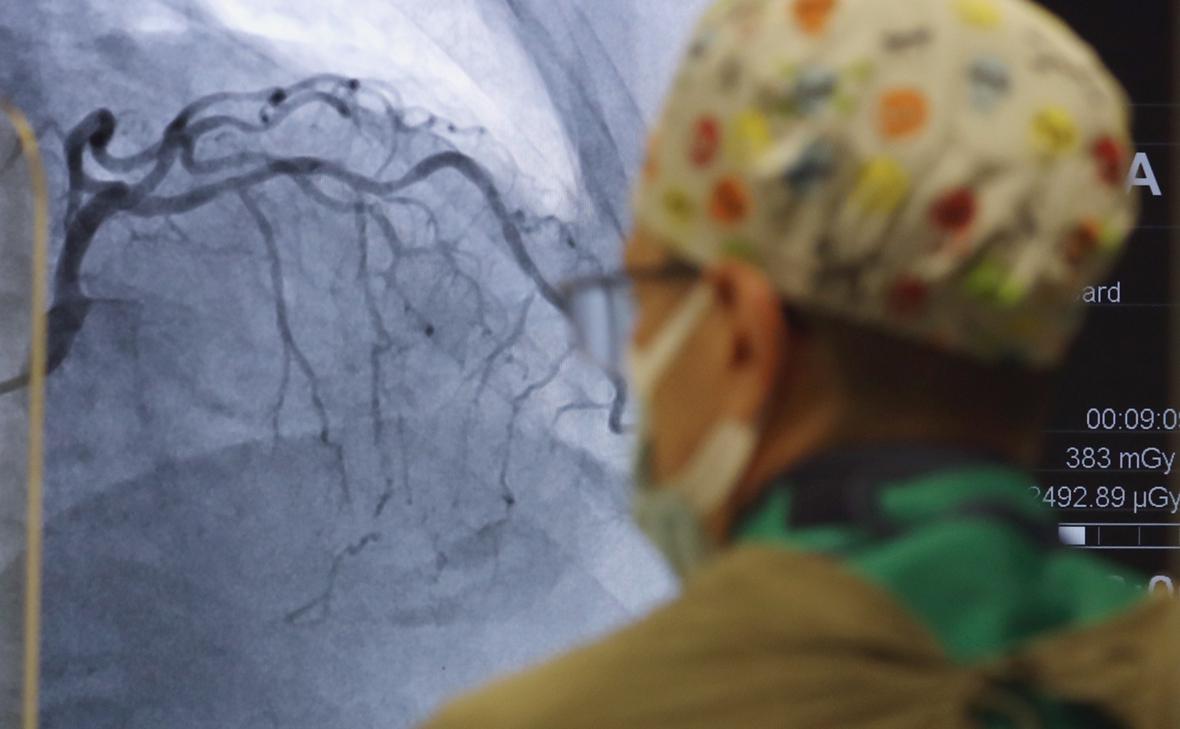

Свыше 80% смертей в России вызваны заболеваниями сердца и сосудов, злокачественными новообразованиями, хроническими респираторными заболеваниями и сахарным диабетом, сообщил глава ВОЗ в Москве

Значительная часть смертей в России связана с четырьмя категориями заболеваний, их перечислил в интервью «РИА Новости» глава офиса Всемирной организации здравоохранения (ВОЗ) в Москве Батыр Бердыклычев.

«Jсновное бремя заболеваний <...> обусловлено прежде всего неинфекционными хроническими заболеваниями, такими как болезни сердца и сосудов, злокачественные новообразования, хронические респираторные заболевания, сахарный диабет. На эти заболевания приходится более 80% всех смертей в стране», — сказал он.

Бердыклычев отметил, что на заболеваемость и смертность влияют такие факторы, как злоупотребление алкоголем, курение, потребление большого количества соли, нездоровое питание, загрязнение воздуха и повышенное артериальное давление.